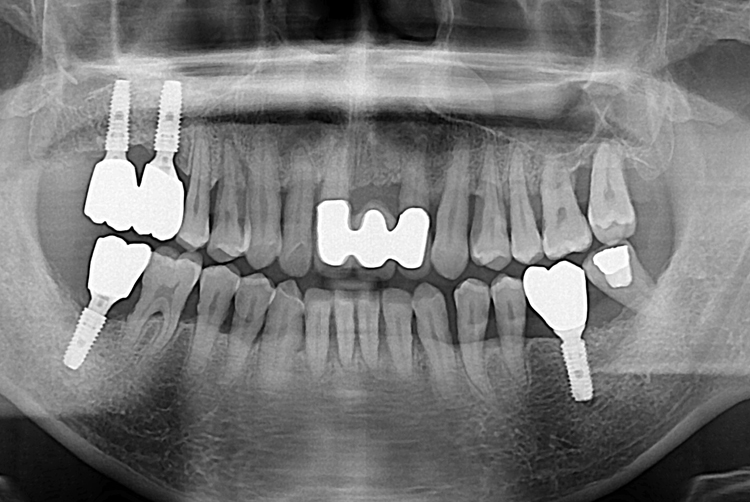

[임플란트] 어금니 임플란트

치료전 : 2017-07-18

세종치과는 많은 환자와 다양한 케이스를 바탕으로

항상 편안한 임플란트 수술을 제공하고자 노력하고,

오래동안 튼튼히 쓸 수 있는 임플란트 수술을 가장 큰 목표로 삼고 있습니다.